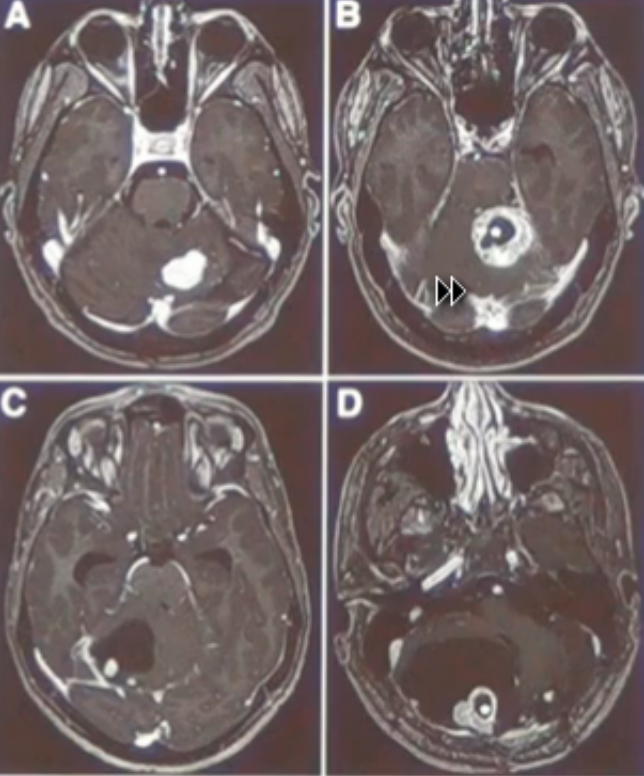

På MR-skanninger er selve hæmangiblastomet kraftigt kontrastopladende. Nogle hæmangioblastomer er omgivet af en cyste, og hvis man foretager MR-skanning et stykke tid efter administration af kontrast kan man se extravasation af kontrast ind i cysten. Nogle hæmangioblastomer er omgivet af ødem, og med tiden kan dette ødem samle sig til en cyste.